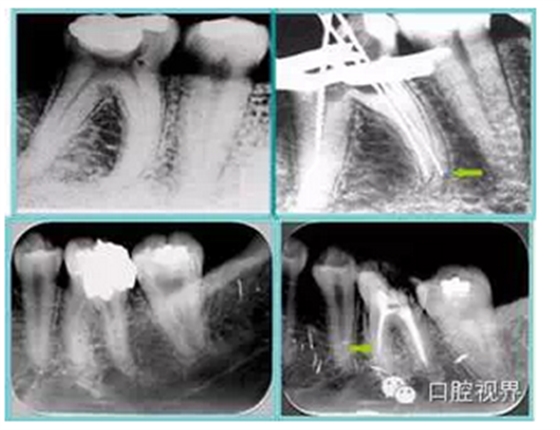

左圖和上圖為干髓治療后牙齒,齲齒疏通后進行根管充填。

( 2 )塑化。

傳統(tǒng)的治療思維:塑化治療后患者需將塑化液清理干凈,達到徹底根管治療目的。

目前的治療思維:以前塑化治療效果好時不必清理干凈塑化液。對于根尖沒有病變的患者,可借助溶解劑建立通路;根尖存在病變的患者往往是塑化治療不理想患者,需要徹底打通通路。

如圖為塑化加根充處理后牙齒 X 線片。